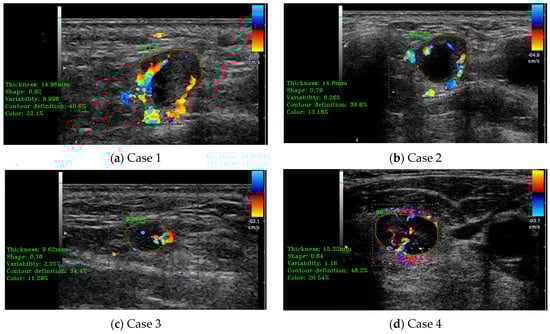

The detection results obtained using the final version of the detection module and the main shape parameters results, including thickness, length, and area, shape form (elliptical vs. circular), shape variability, and the main contour analysis parameter (contour sharpness/definition), are shown in Figure 7.

Figure 7.

(a–d) illustrate cases of lymph node (LN) automatic detection using B-mode ultrasound (US) and shape parameter evaluation. The red contour represents the manually delineated region by the doctor, while the green contour corresponds to the system’s automatically detected LN boundary. The percentage value indicates the detection accuracy.

3.3. Doppler Analysis Module Performance Evaluation

In this case, the medical indicators for B-mode US evaluation that were also valid for Doppler-mode US were kept. Besides those, some specific indicators and algorithms were developed. The specific Doppler ultrasound indicators evaluated some extra parameters, such as the vascularity ratio and the vascularity position presented in Figure 8. On the left side of the images are printed, in a green color, the numerical results of several indicators, including the vascularity ratio, in the percentages named “Color”. As can be seen for all the cases presented in Figure 8, the percentages are below the defined cut-off threshold for metastasis indication.

Figure 8.

(a–d) illustrate cases of lymph node (LN) automatic detection using Doppler-mode ultrasound (US), incorporating shape parameter evaluation and Doppler US indicator assessment for enhanced accuracy. The red contour represents the manually delineated region by the doctor, while the green contour corresponds to the system’s automatically detected boundary. The percentage value indicates the detection accuracy.

3.4. Elastography Analysis Module Performance Evaluation

In this case, the medical indicators for B-mode US evaluation that were also valid for elastography were kept. Besides those, some specific indicators and algorithms were developed. The specific elastography indicators evaluated some extra parameters like tissue rigidity. The two sub-algorithms for the detection of the B-mode US region and the colored elastography region were also evaluated; the results are presented in Figure 9. In a similar manner to the Doppler analysis module, on the left side of the images are printed, in a green color, the numerical results of several indicators, including the percentage of the analyzed color classes “Red”, “Green”, and “Blue”. For all the cases presented in Figure 9, the combined percentage of “green” and “blue” was above the defined cut-off threshold for metastasis.

Figure 9.

(a–d) illustrate cases of lymph node (LN) automatic detection using elastography, integrating shape parameter evaluation and elastography color indicator assessment for improved diagnostic precision. The red contour represents the manually delineated region by the doctor, while the green contour corresponds to the system’s automatically detected boundary. The percentage value indicates the detection accuracy.